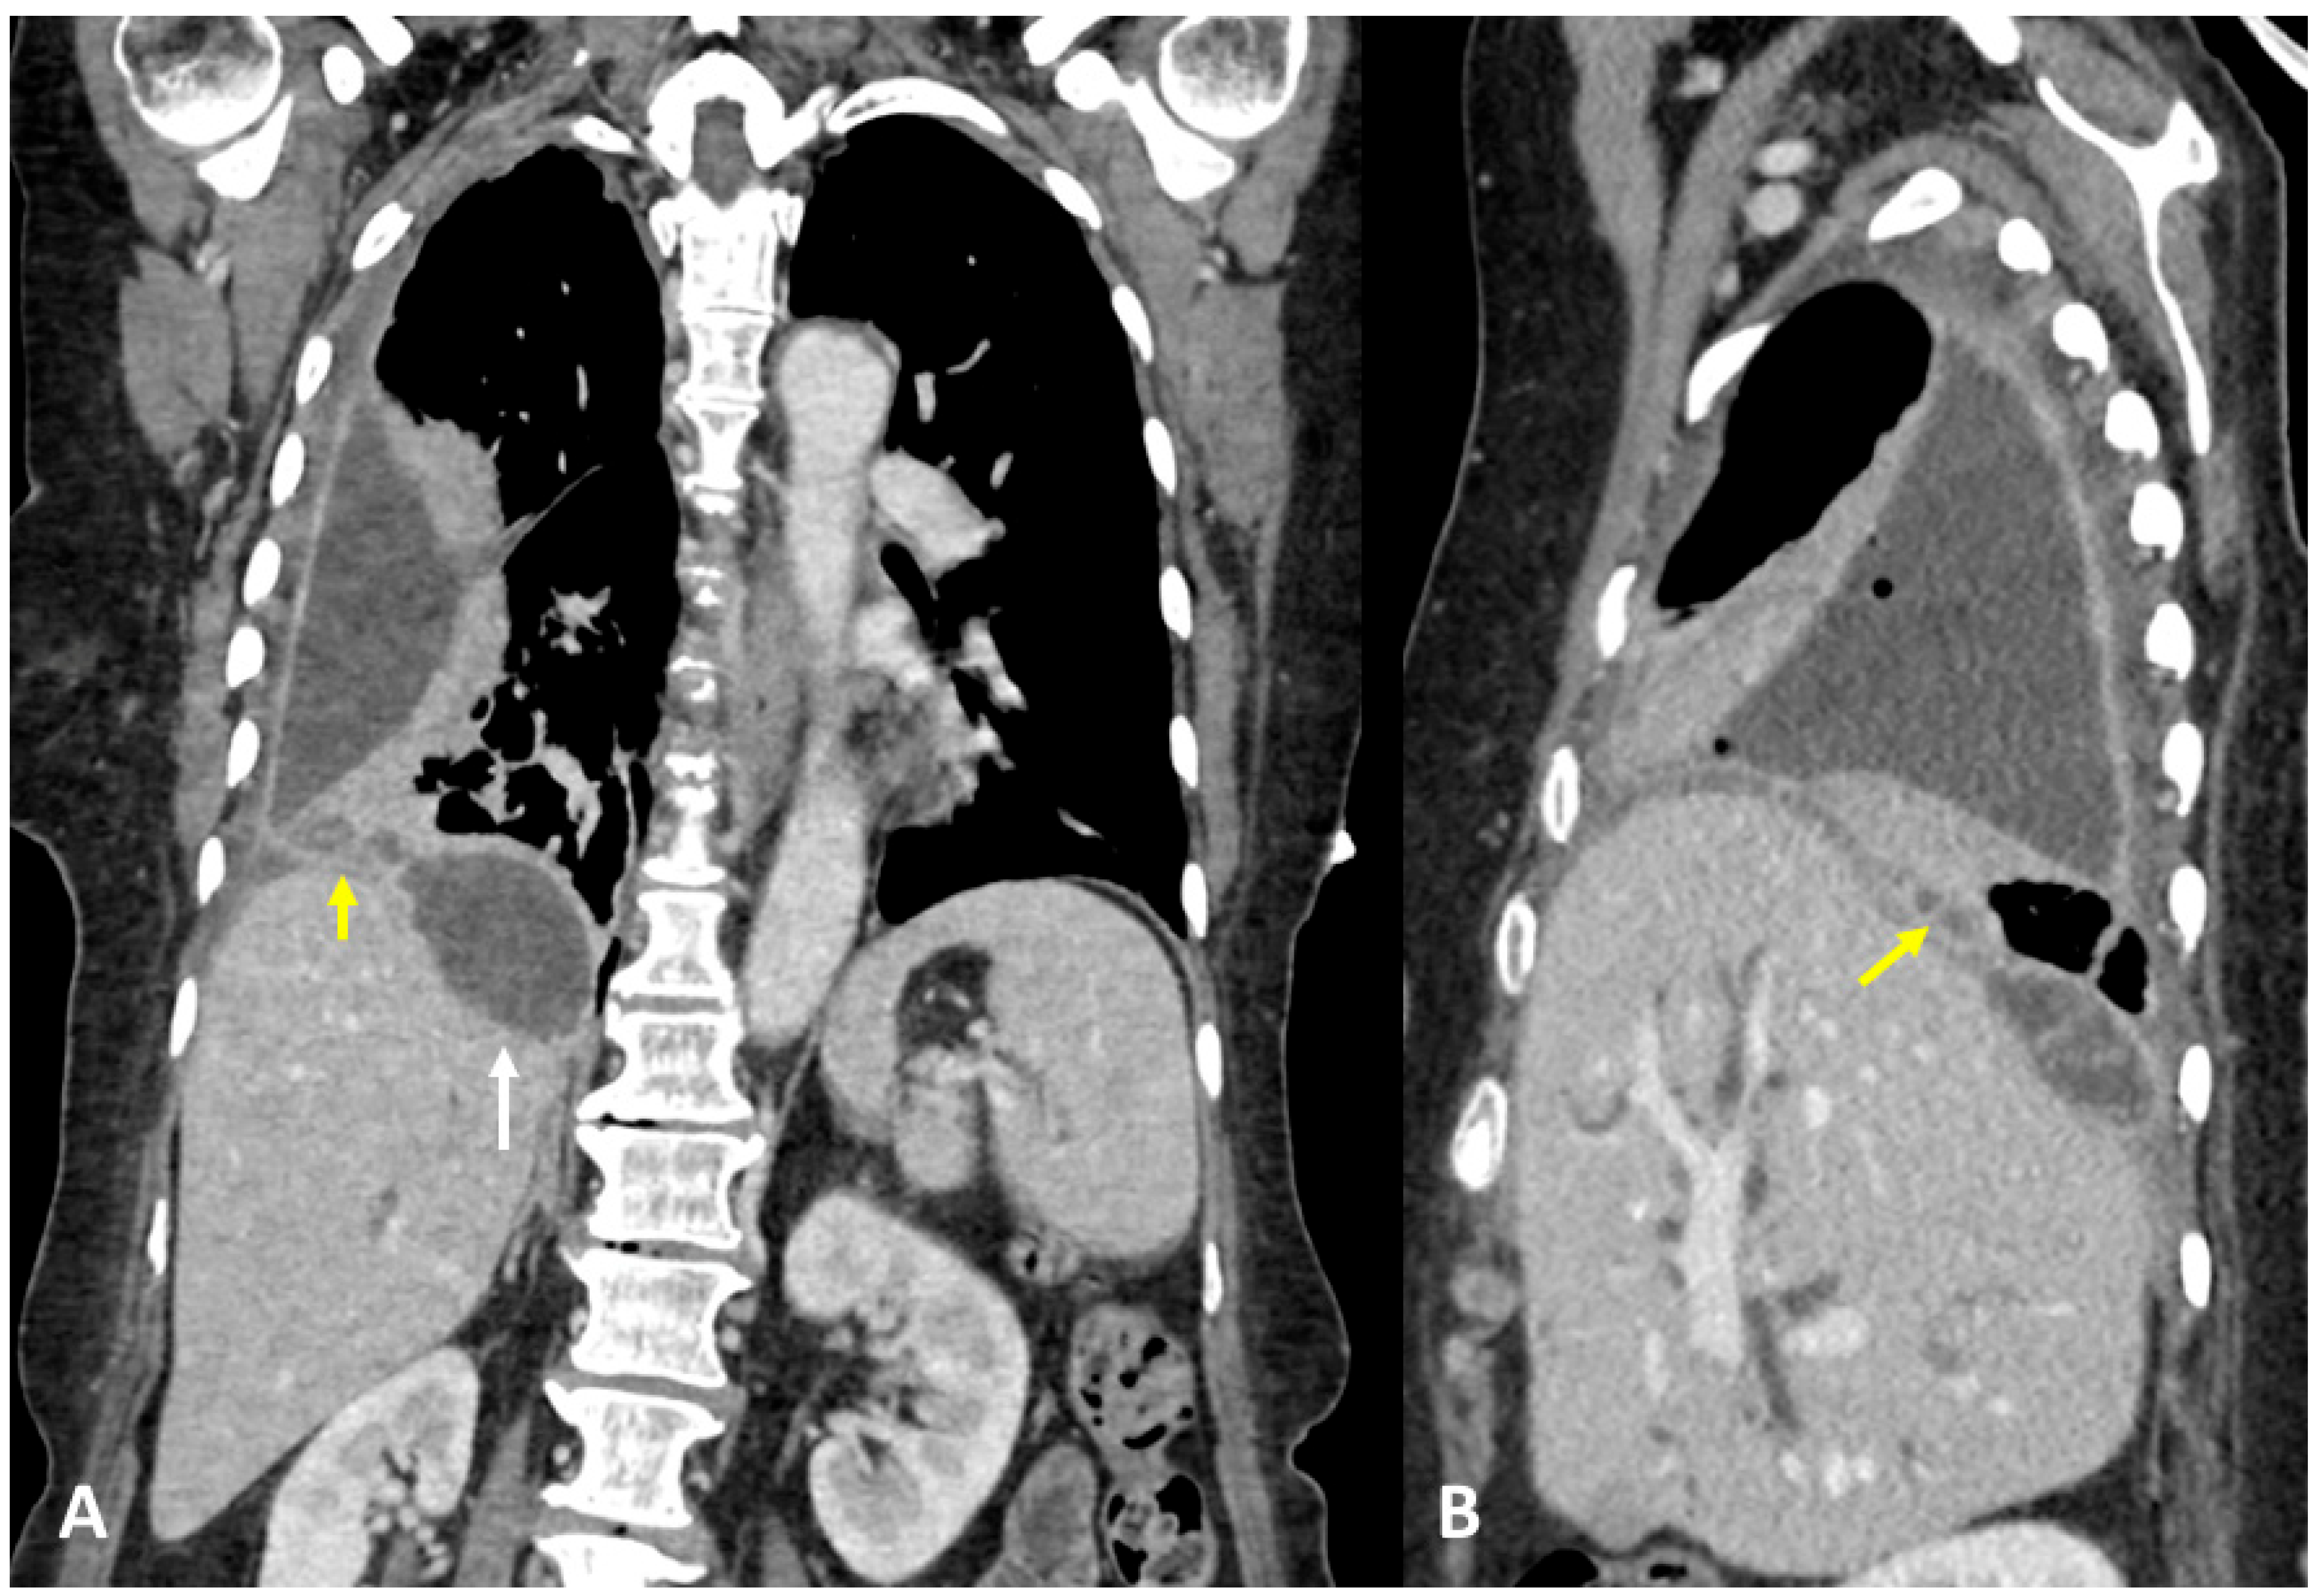

A 91-year-old man referred in an ER setting was complaining of acute chest pain and abdominal pain in the upper right side. The patient had diabetes, arterial hypertension, and chronic ischemic heart disease treated via aorto-coronary bypass. Physical examination revealed diminished breath sounds over the right hemithorax and a positive Murphy sign. Laboratory routine tests showed mild neutrophilia, increased CRP, and bilirubin levels. The patient underwent abdominal ultrasound showing thickened gallbladder walls, a gallstone, and the thickening of pericholecystic adipose tissue especially at the fundus where a hypoechogenic fluid collection was visualized. Chest X-ray showed right basal pleural effusion and atelectasis of adjacent lung parenchyma. The patient underwent contrast-enhanced thoraco-abdominal CT showing cholecystitis, edema, and the thickening of pericholecystic adipose tissue with small air bubbles. CT also showed an abscess at the gallbladder fundus adjacent to the right diaphragmatic pillar. Pleural effusion and parenchymal consolidation of the right lower lobe were associated with one another (Figure 4A,B). The CT diagnosed TBF, caused by cholecystitis complicated by an abscess that had eroded the right diaphragmatic pillar leading to biliopleural fistula formation. The patient was treated initially through percutaneous drainage of the pericholecystic abscess and with antibiotic therapy, followed by cholecystectomy surgery with definitive removal of the abscess remnants and closure of the transdiaphragmatic fistula.

Figure 4.

(A,B) Contrast-enhanced CT and coronal (A) and sagittal planes (B) show cholecystitis, edema, and thickening of pericholecystic adipose tissue, as well as an abscess at the gallbladder fundus adjacent to the right diaphragmatic pillar (arrow).

A 63-year-old woman, with no significant pathological history, was admitted to the ER, complaining about fever, cough, and abdominal pain. Physical examination revealed a positive Murphy sign. Laboratory routine tests showed mild neutrophilia and increased CRP and GT levels. The patient underwent abdominal ultrasound showing thickened gallbladder walls and gallstones, with pericholecystic fluid and biliary tract dilatation, and a hypoechogenic lesion was noted in the subdiaphragmatic liver parenchyma. Chest X-ray showed right basal pleural effusion and atelectasis of adjacent lung parenchyma. The patient underwent contrast-enhanced thoraco-abdominal CT, showing right pleural empyema with gas bubbles, cholecystitis, and gallstones, and a large collection was located in between the diaphragm and the liver. A fistulous tract was also noted (Figure 5A,B). MRCP confirmed the fistulous tract between the collection and the empyema (Figure 6). The patient underwent ERCP to remove the gallstones and to place a biliary stent. At the same time, the subdiaphragmatic collection was drained and antibiotic therapy was started. Subsequently, the patient underwent surgery for cholecystectomy, lysis of the liver adhesions, and closure of the transdiaphragmatic fistula.

Figure 5.

(A,B) Contrast-enhanced CT and coronal (A) and sagittal planes (B) demonstrate a right pleural empyema with gas bubbles and a collection (white arrow) located between the diaphragm and the liver. (A) Definite fistulous tract is noted (yellow arrows).